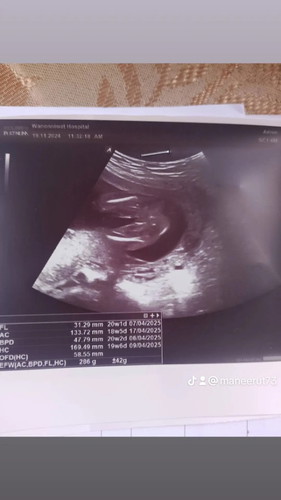

ซาวด์โรงบาลรัฐตอน20วิก

คุณหมอว่าผุหญิงจะใช้หรือเปล่าค่ะ

ถ้าชายน่าจะเป็นเป็นลูกๆ นะคะ มุมนี้ 😂

น่าจะเป็นผู้ ญ คะเเม่